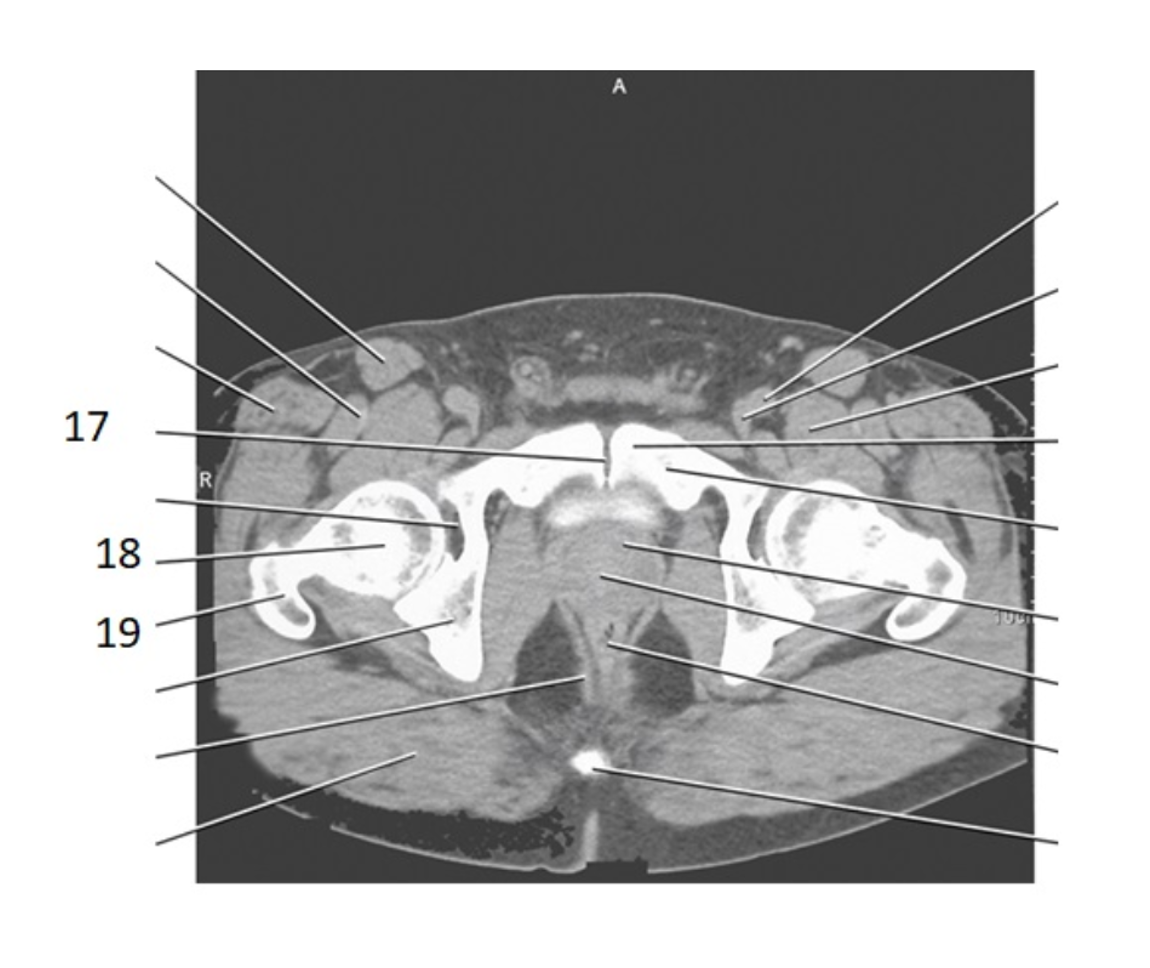

17

pubic bone

20

prostate

31

seminal vesicles

7

SI joint

28

bladder

3

psoas

pubic symphysis

28 women

cervix

25 women

uterus